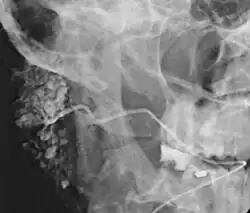

Sialografie bei Verdacht auf Sjögren-Syndrom.

Die Sonografie kann die Diagnose in unklaren Fällen stützen. Die Sialografie kann bei chronischen Verläufen wertvolle Hinweise zur Differentialdiagnose geben. Bei einer chronisch-rezidivierenden Sialadenitis findet sich ein Bild wie bei einem „belaubten Baum“. Dagegen sind viele Drüsengänge bei einem Sjögren-Syndrom zerstört („rarefiziert“), sodass sich das Bild eines „entlaubten Baumes“ ergibt. Bei einer akuten Speicheldrüsenentzündung ist die Sialografie kontraindiziert.